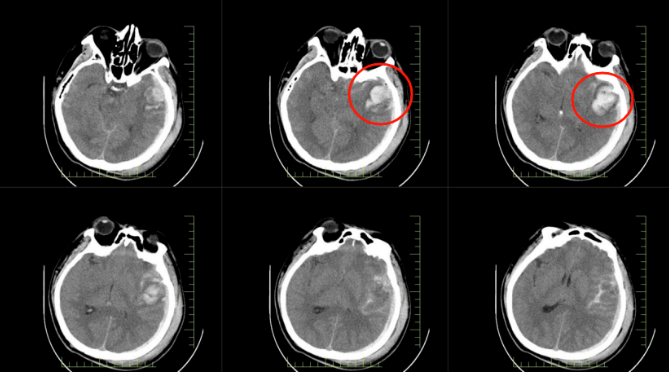

患者郭先生因高處墜落,送達(dá)醫(yī)院時已陷入昏迷。經(jīng)急診全面檢查,被確診為顱腦損傷重型、腦挫裂傷伴腦內(nèi)血腫、創(chuàng)傷性蛛網(wǎng)膜下腔出血等多項(xiàng)嚴(yán)重病癥。顱內(nèi)出血、顱壓驟升,每一項(xiàng)診斷都如同高懸的達(dá)摩克利斯之劍,威脅著患者的生命。

*患者顱內(nèi)出血影像圖

*患者顱內(nèi)術(shù)后影像圖